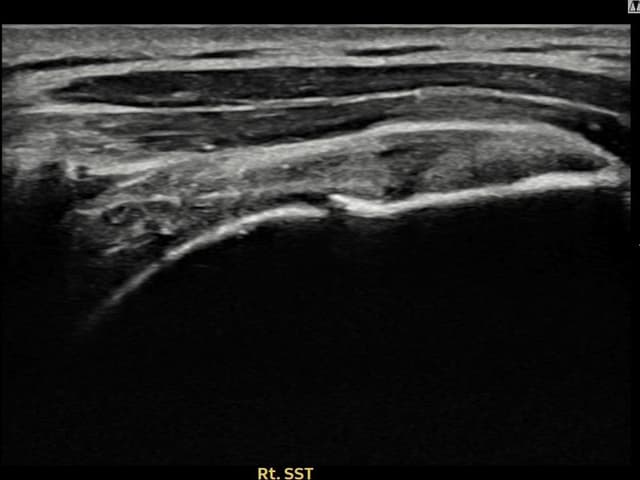

実際の患者様の施術前後の超音波画像。

手術なしで実現できる回復をご確認ください。

[経過期間: 23.10.23~24.01.04]

[縫縮術] 超音波検査にて左 棘上筋腱 関節面側部分断裂(8mm × 3mm (腱厚の約33%欠損))を確認。縫縮術施行後、腱の連続性が回復し、日常生活に復帰されました。